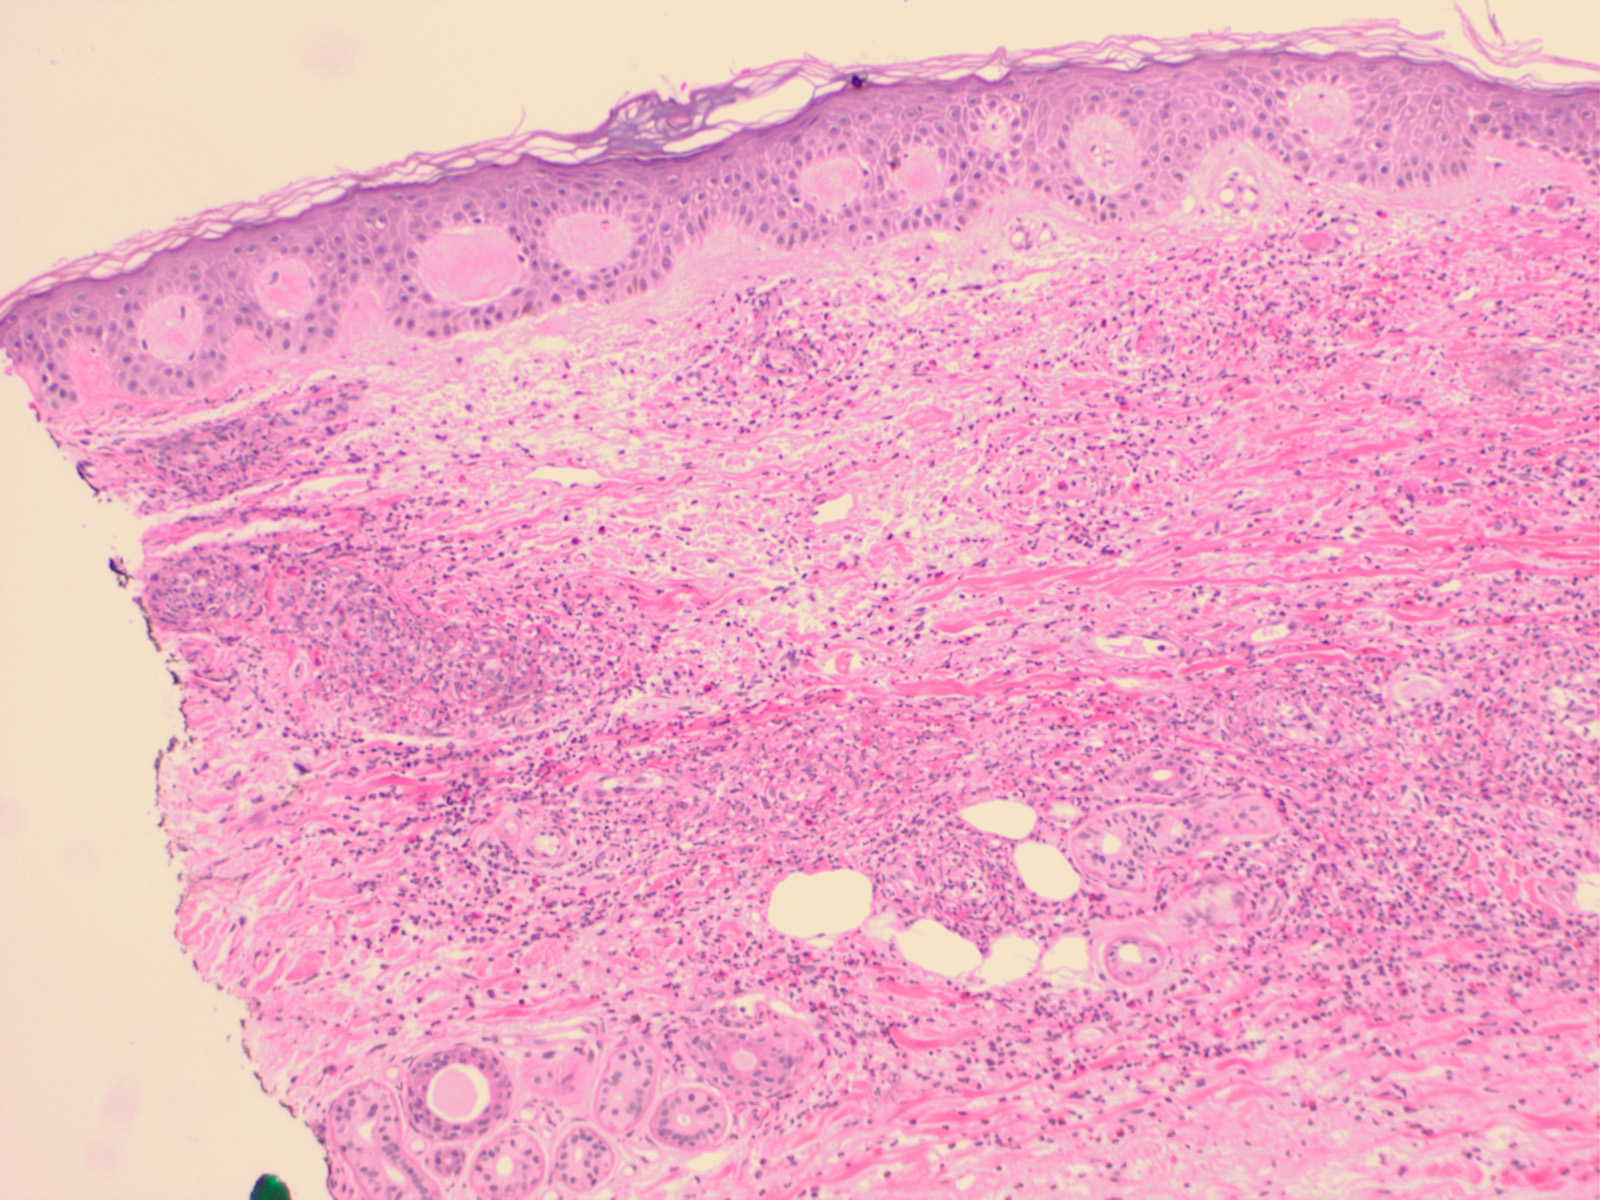

Henoch-Schonlein purpura cannot be distinguished histologically from other forms of LCV, although the degree of vascular damage is often not as great as that usually observed in typical LCV. Immunofluorescence studies typically demonstrate the deposition of IgA in capillaries (Fig. 8-11). Such a limited extent of vascular damage is also commonly observed in urticarial vasculitis (see text following), and clinical findings may be necessary for distinction of H-SP from urticarial vasculitis. IgA-associated vasculitis may occur outside of the symptom complex of H-SP (52). However, serologic detection of IgA-fibronectin aggregates may be associated with greater likelihood of renal or systemic disease in patients with cutaneous LCV .